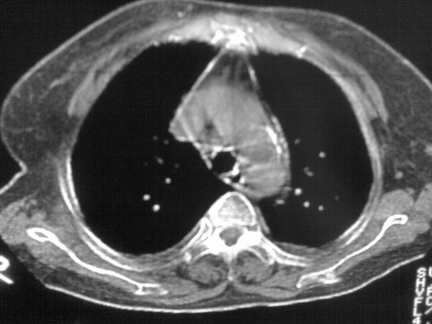

标题: CT13142:女 80 胸闷、气短、1w [打印本页]

标题: CT13142:女 80 胸闷、气短、1w

右肺炎性变,双侧甲状腺肿,胸膜肥厚。

右肺炎性变

双侧胸腔积液

缩窄性心包炎

左室为主的心脏增大。

胸膜肥厚,

气管,支气管软骨钙化。

右肺感染;双侧胸腔少量积液,心影增大,可能与心功不全有关;胸内甲状腺肿。

右肺炎性变,双侧甲状腺肿,胸膜肥厚,心影增大考虑心功能不全.

胸内甲状腺肿;右肺感染;双侧胸腔少量积液。

胸内甲状腺肿;右肺中叶感染;双侧胸腔少量积液;心影增大,考虑有心功能不全。